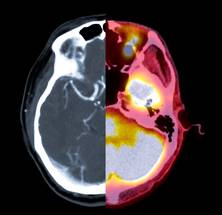

Participants who were eligible based on blood tests also underwent positron emission tomography (PET) scans, brain scans that are used to directly measure amyloid buildup in the brain. Among “plasma eligible” participants (those who met the blood test cutoff), individuals from all racial and ethnic groups were equally likely to be eligible to participate based on PET scan data. The study was just published in Alzheimer’s & Dementia: The Journal of the Alzheimer’s Association.

The researchers collected blood from each participant and calculated amyloid levels, using a liberal threshold to determine who was considered eligible for inclusion in the clinical trial. The trial requires a participant to have 20 centiloids or more of amyloid, but researchers lowered the cutoff to 11 centiloids to avoid excluding participants who might be just below the typical threshold. Centiloids are units in a standardized method of measuring amyloid plaque in the brain based on PET imaging.

Then, the researchers collected and analyzed PET scans from the 1,724 participants who were deemed plasma-eligible for the clinical trial. All racial and ethnic groups in the study were equally likely to meet inclusion criteria based on PET scans.